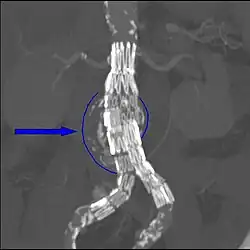

Une endoprothèse vasculaire peut être un stent. Un stent couvert est en fait une pièce de métal cylindrique mise en place dans un vaisseau. L’aspect extérieur évoque celui d’un ressort (présence de mailles de formes variables suivant le type). Il en existe deux sortes :

- les stents non couverts : support endovasculaire servant dans le cadre des dilatations des rétrécissements (« ou sténoses ») des vaisseaux de façon à empêcher la récidive (« resténose »). Dans ce cas le grillage est perméable ;

- les stents « couverts » : il s’agit de stents recouverts d’une fine membrane synthétique par-dessus le maillage. Ils sont imperméables et peuvent donc être utilisés pour prévenir ou bien traiter les hémorragies.